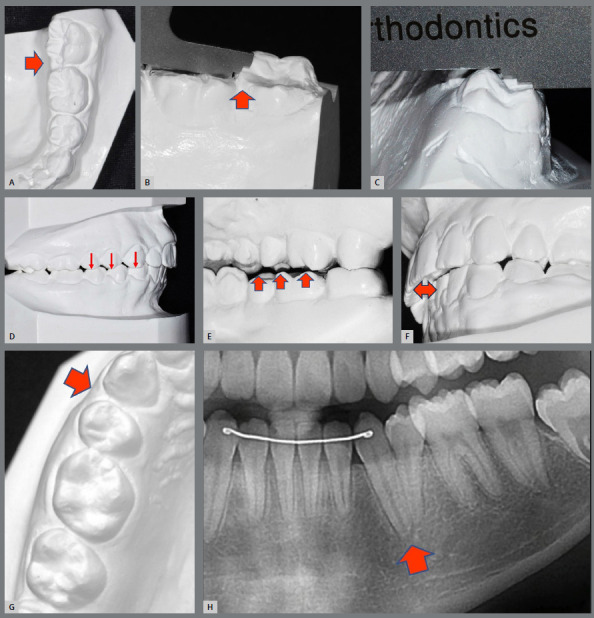

Results: A total of 447 orthodontic records was included. Orthodontic finishing errors were often observed, and no case was completely perfect. In the total CRE score, an average of 15 points was discounted for each case. Most frequently found issues involved problems with alignment, buccolingual inclination, marginal ridge, and occlusal relationship. The median DI score for initial case complexity was 22.0 (range 10.0 - 67.0). There was no significant correlation between the DI and CRE scores (p=0.106).

Conclusion: Orthodontic finishing errors are inevitable, even in well-finished board-approved cases. Rotation, excessive buccolingual inclination, and discrepancies in marginal ridges are the most frequently observed areas of concern, in that order. Moreover, while case complexity, determined by DI, can impact orthodontic planning and pose challenges for clinicians, the study did not consider it a determining factor in predicting treatment outcomes.